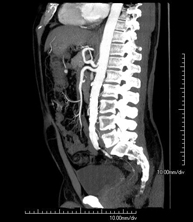

Prova diagnòstica no invasiva que consisteix en l'estudi de l'artèria aorta abdominal a través de l'obtenció d'imatges d'alta definició anatòmica mitjançant l'ús d'un equip de TC (Tomografia Computeritzada) i de contrast iodat. La qualitat de les imatges permet realitzar reconstruccions en 2D i 3D gràcies a estacions de treball especialitzades en l'estudi arterial. Està indicat en aquells pacients amb malaltia vascular (arteriosclerosi), en aneurismes d'aorta, en pacients amb dolor abdominal de possible origen vascular, en estudis prequirúrgics de lesions adjacents a l'aorta abdominal com a "mapa" vascular. La informació obtinguda de manera no invasiva és indispensable per als pacients que requereixen tractament percutani o quirúrgic. En aquells pacients que només requereixen seguiment de les lesions vasculars, aquesta tècnica és la tècnica no invasiva d'elecció juntament amb l'angio-RM. - Angio-TC Artèries renals

Prova diagnòstica no invasiva que consisteix en l'estudi de l'artèria aorta abdominal amb l'obtenció d'imatges d'alta definició anatòmica mitjançant l'ús d'un equip de TC (Tomografia Computaritzada) i contrast iodat. La qualitat de les imatges permet realitzar reconstruccions en 2D i 3D gràcies a estacions de treball especialitzades en l'estudi arterial. Està indicat en aquells pacients que pateixen malaltia vascular (arteriosclerosi), aneurismes d'aorta, en pacient amb dolor abdominal d'un possible origen vascular, en estudis prequirúrgics de lesions adjacents a l'aorta abdominal com el "mapa" vascular, etc. La informació obtinguda de forma no invasiva és indispensable per als pacients que requereixen tractament percutani o quirúrgic. En aquells pacients que només requereixen un seguiment de les lesions vasculars, aquesta tècnica és la tècnica no invasiva d'elecció juntament amb l'angio RM. - Angio TC d'artèries renals